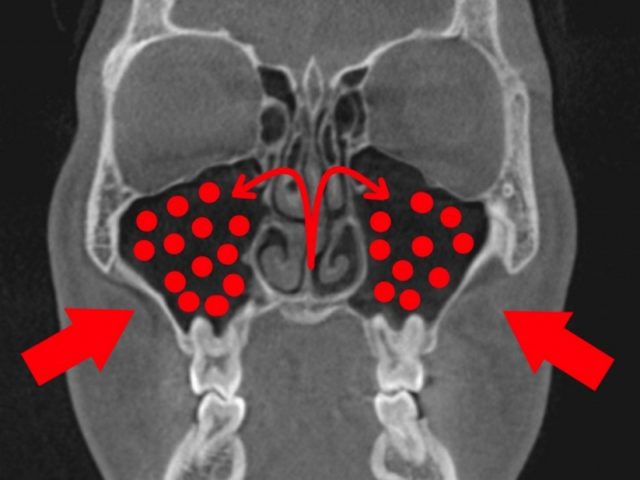

歯性上顎洞炎に なりやすい人 なりにくい人

歯性上顎洞炎になりやすい人

歯根と、上顎洞が近い人です。

上は、上顎洞内に、

大臼歯の歯根が

飛び出しています。

もし、この根が化膿すると、

上顎洞に炎症が波及しやすいでしょう。

この様な方は、

歯性上顎洞炎になりやすいと思われます。

歯性上顎洞炎になりにくい人

上は、上の大臼歯の歯根と、

上顎洞の距離がある方です。

もし、歯根が化膿しても、

炎症は、上顎洞へは、波及しにくいでしょう。

歯性上顎洞炎には、なりにくいと思われます。